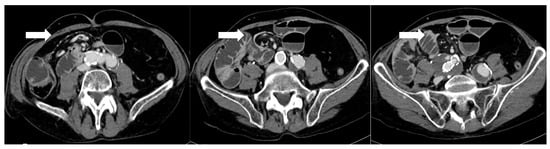

CT’s strengths lie in its high sensitivity for extraluminal gas and fluid, its ability to detect subtle signs like focal mesenteric fat stranding or free air under the diaphragm (which on CT can be discerned even in small volumes), and its capacity to evaluate the entire abdomen for alternative diagnoses. CT can also identify complications like small bowel obstruction from adhesions or hernias, and vascular problems (e.g., splenic infarcts from short gastric artery injury or portal vein thrombosis), which occasionally occur after bariatric surgery [20]. If active bleeding is suspected (for example, a late marginal ulcer hemorrhage or bleeding at a staple line), a CT angiography protocol can be employed to look for contrast extravasation in arterial phase; this can guide interventional radiology if an embolization is needed [36]. One significant strength of CT is in diagnosing internal hernias and small-bowel obstructions, particularly in RYGB patients. An internal hernia occurs when bowel loops protrude through a mesenteric defect created by the surgery (such as the transverse mesocolon defect in a retrocolic Roux limb, the mesenteric gap at the jejunojejunostomy, or Petersen’s space between the Roux limb and transverse colon mesentery) [37]. Classic CT signs of internal hernia after RYGB include a swirled appearance of the mesenteric root fat and vessels (the “whirl” or swirl sign), which reflects the twisting of mesentery as bowel herniates [38] (Figure 3). Other CT hallmarks are clustered, ectopic small-bowel loops (often congregated in an abnormal location such as the left upper quadrant or behind the mesenteric root) with evidence of obstruction (dilated proximal loops and decompressed distal bowel) [39]. Additional reported signs include engorged and stretched mesenteric vessels converging toward the hernia orifice, beaking and crowding of the superior mesenteric vein, the “hurricane eye” sign (a tubular cluster of mesenteric fat surrounded by bowel loops on cross-section), and displacement of the normal jejunojejunal anastomosis position [40]. However, a study by Lockhart et al. and subsequent analyses indicated that mesenteric swirl carries the highest sensitivity and specificity for internal hernia and should be considered pathognomonic in the appropriate clinical context [41]. CT is equally valuable in characterizing fistulous connections and differentiating them from free leaks. For example, a known late complication of RYGB is the formation of a gastro-gastric fistula (GGF), wherein a communication develops between the gastric pouch and the excluded stomach due to staple-line dehiscence. On a CT with oral contrast, a GGF is diagnosed when contrast that was swallowed (entering the pouch) is seen opacifying the excluded stomach, while notably not filling the downstream biliopancreatic limb or duodenum [42].

Figure 3.

After 5 days from sleeve gastrectomy, axial post-contrast CT scans showing an angulated course of the duodenojejunal junction to the right of the midline, with evidence of a mesenteric “whirlpool sign,” suggestive of intestinal malrotation (arrows). The copyright of this figure belongs to the authors.